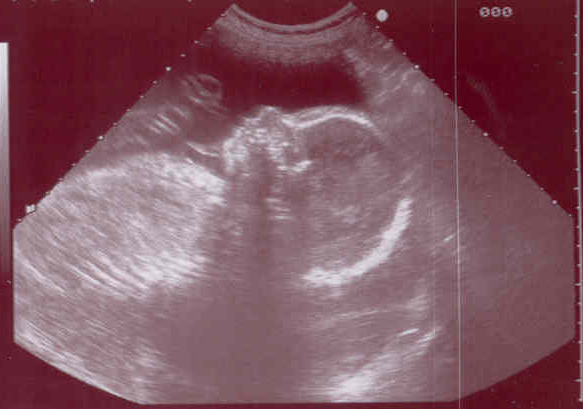

Resulta que la protagonista se queda embarazada, pero no tiene muy claro si quiere seguir adelante con el embarazo o no. Y su duda no deriva de si desea tener un hijo en ese momento de su vida o si dispondrá de recursos para poder ser madre. No, el problema es que el padre de la criatura es una persona con discapacidad intelectual y a ella le produce pánico que el bebé pueda heredar esa característica.

Por no hablar de que no existe prueba prenatal en el mundo que pueda descartar que un bebé vaya a nacer con alguna discapacidad o afección genética. No existe.